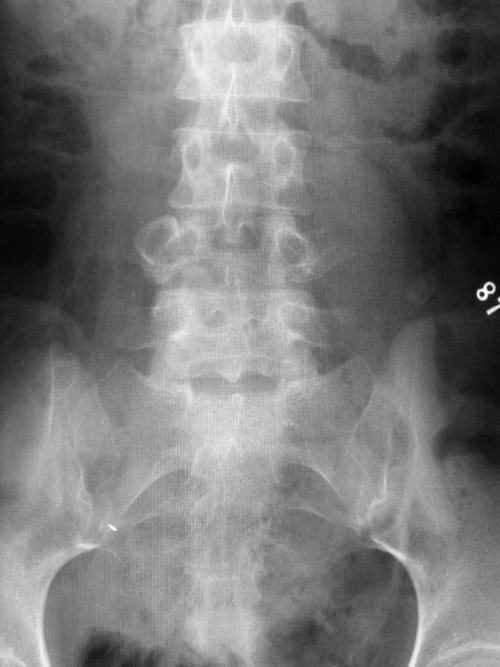

Case13:F,4y;腰痛1月余,加重半月。

文章插图